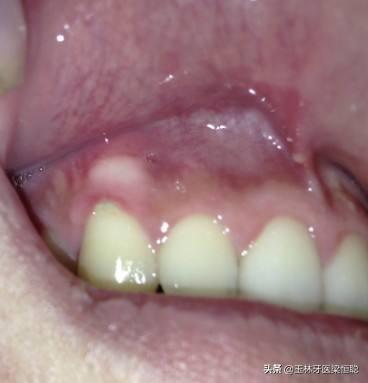

臨床上,我們常常遇到患者說“牙齦上鼓了個包,硬硬的”,或鑲牙的老人說“牙床壓著疼”,通??赡苁浅霈F(xiàn)了牙槽骨骨質(zhì)增生。

口腔內(nèi)牙槽骨的骨質(zhì)增生是指牙齦區(qū)域的牙槽骨出現(xiàn)骨質(zhì)增生性突起,在臨床上比較常見。

骨質(zhì)增生的形式多種多樣,因所在部位不同而有其各自的特點,在口腔中多表現(xiàn)多圓錐狀突起或小骨刺,一般沒有的臨床癥狀,有時候伴有輕微的疼痛,可以通過X光攝片清晰地辨認(rèn)骨質(zhì)增生的部位和增生的程度。